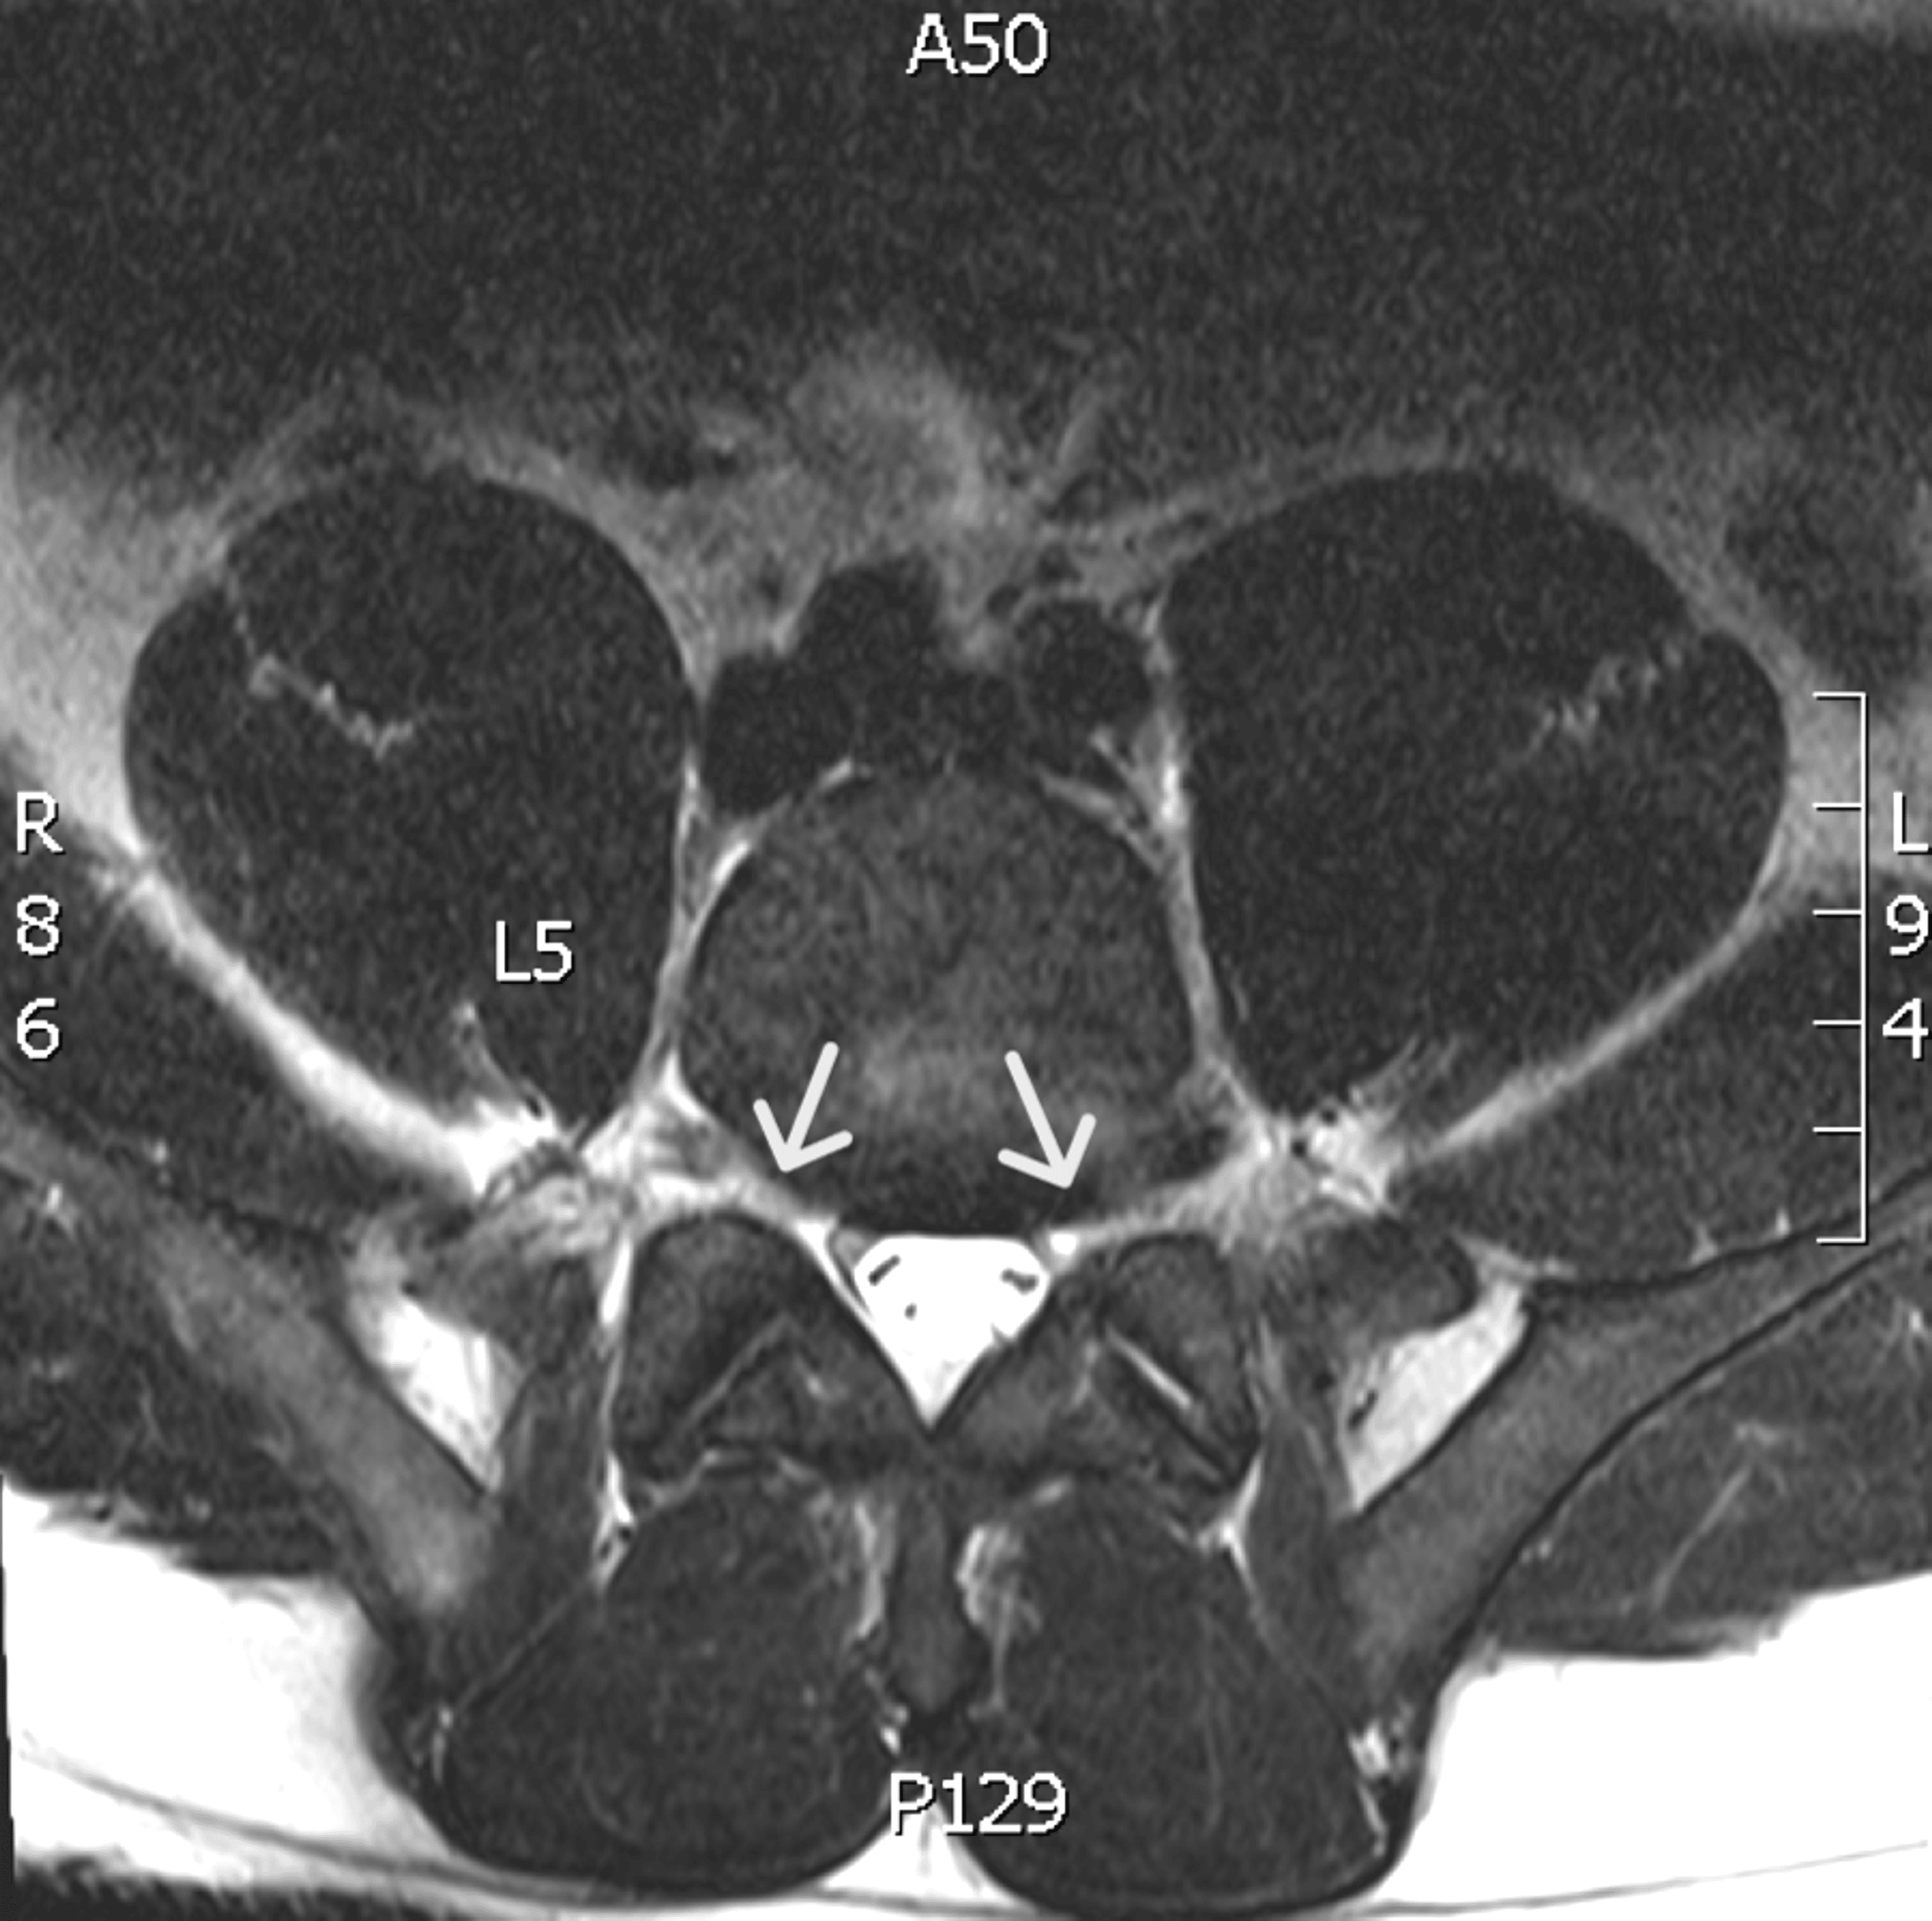

From www.cureus.com

Cureus Livedoid Vasculopathy with Severe Debilitating Neuropathy in a Athletes With Neuropathy Neuropathic pain is not uncommon to encounter in athletes although not always recognised. Now he is an example for his contemporaries confronting diabetes and neuropathy. Jerry mathers embodied an american ideal in leave it to beaver from 1957 to 1963. Neuropathic pain, where a person might feel pain from any part of their body, is nerve pain that occurs after. Athletes With Neuropathy.

Cureus Livedoid Vasculopathy with Severe Debilitating Neuropathy in a Athletes With Neuropathy Neuropathic pain is not uncommon to encounter in athletes although not always recognised. How to know when your pain is actually a symptom of nerve damage. The warriors are officially listing looney as out for an unspecified amount of time as he searches for answers on how best to treat and manage his neuropathy. We tapped 3 experts to explain. Athletes With Neuropathy.

Cureus Livedoid Vasculopathy with Severe Debilitating Neuropathy in a Athletes With Neuropathy How to know when your pain is actually a symptom of nerve damage. Athletes with persistent numbness in the hands and feet may have a peripheral neuropathy or cervical or lumbar stenosis. Logging miles during training can cause significant. The warriors are officially listing looney as out for an unspecified amount of time as he searches for answers on how. Athletes With Neuropathy.

Cureus Livedoid Vasculopathy with Severe Debilitating Neuropathy in a Athletes With Neuropathy Logging miles during training can cause significant. Researchers use several animal models to understand the utility of exercise as a treatment for neuropathic pain by employing different behavioral tests to understand. Jerry mathers embodied an american ideal in leave it to beaver from 1957 to 1963. We tapped 3 experts to explain when it could signal something more serious. Now. Athletes With Neuropathy.